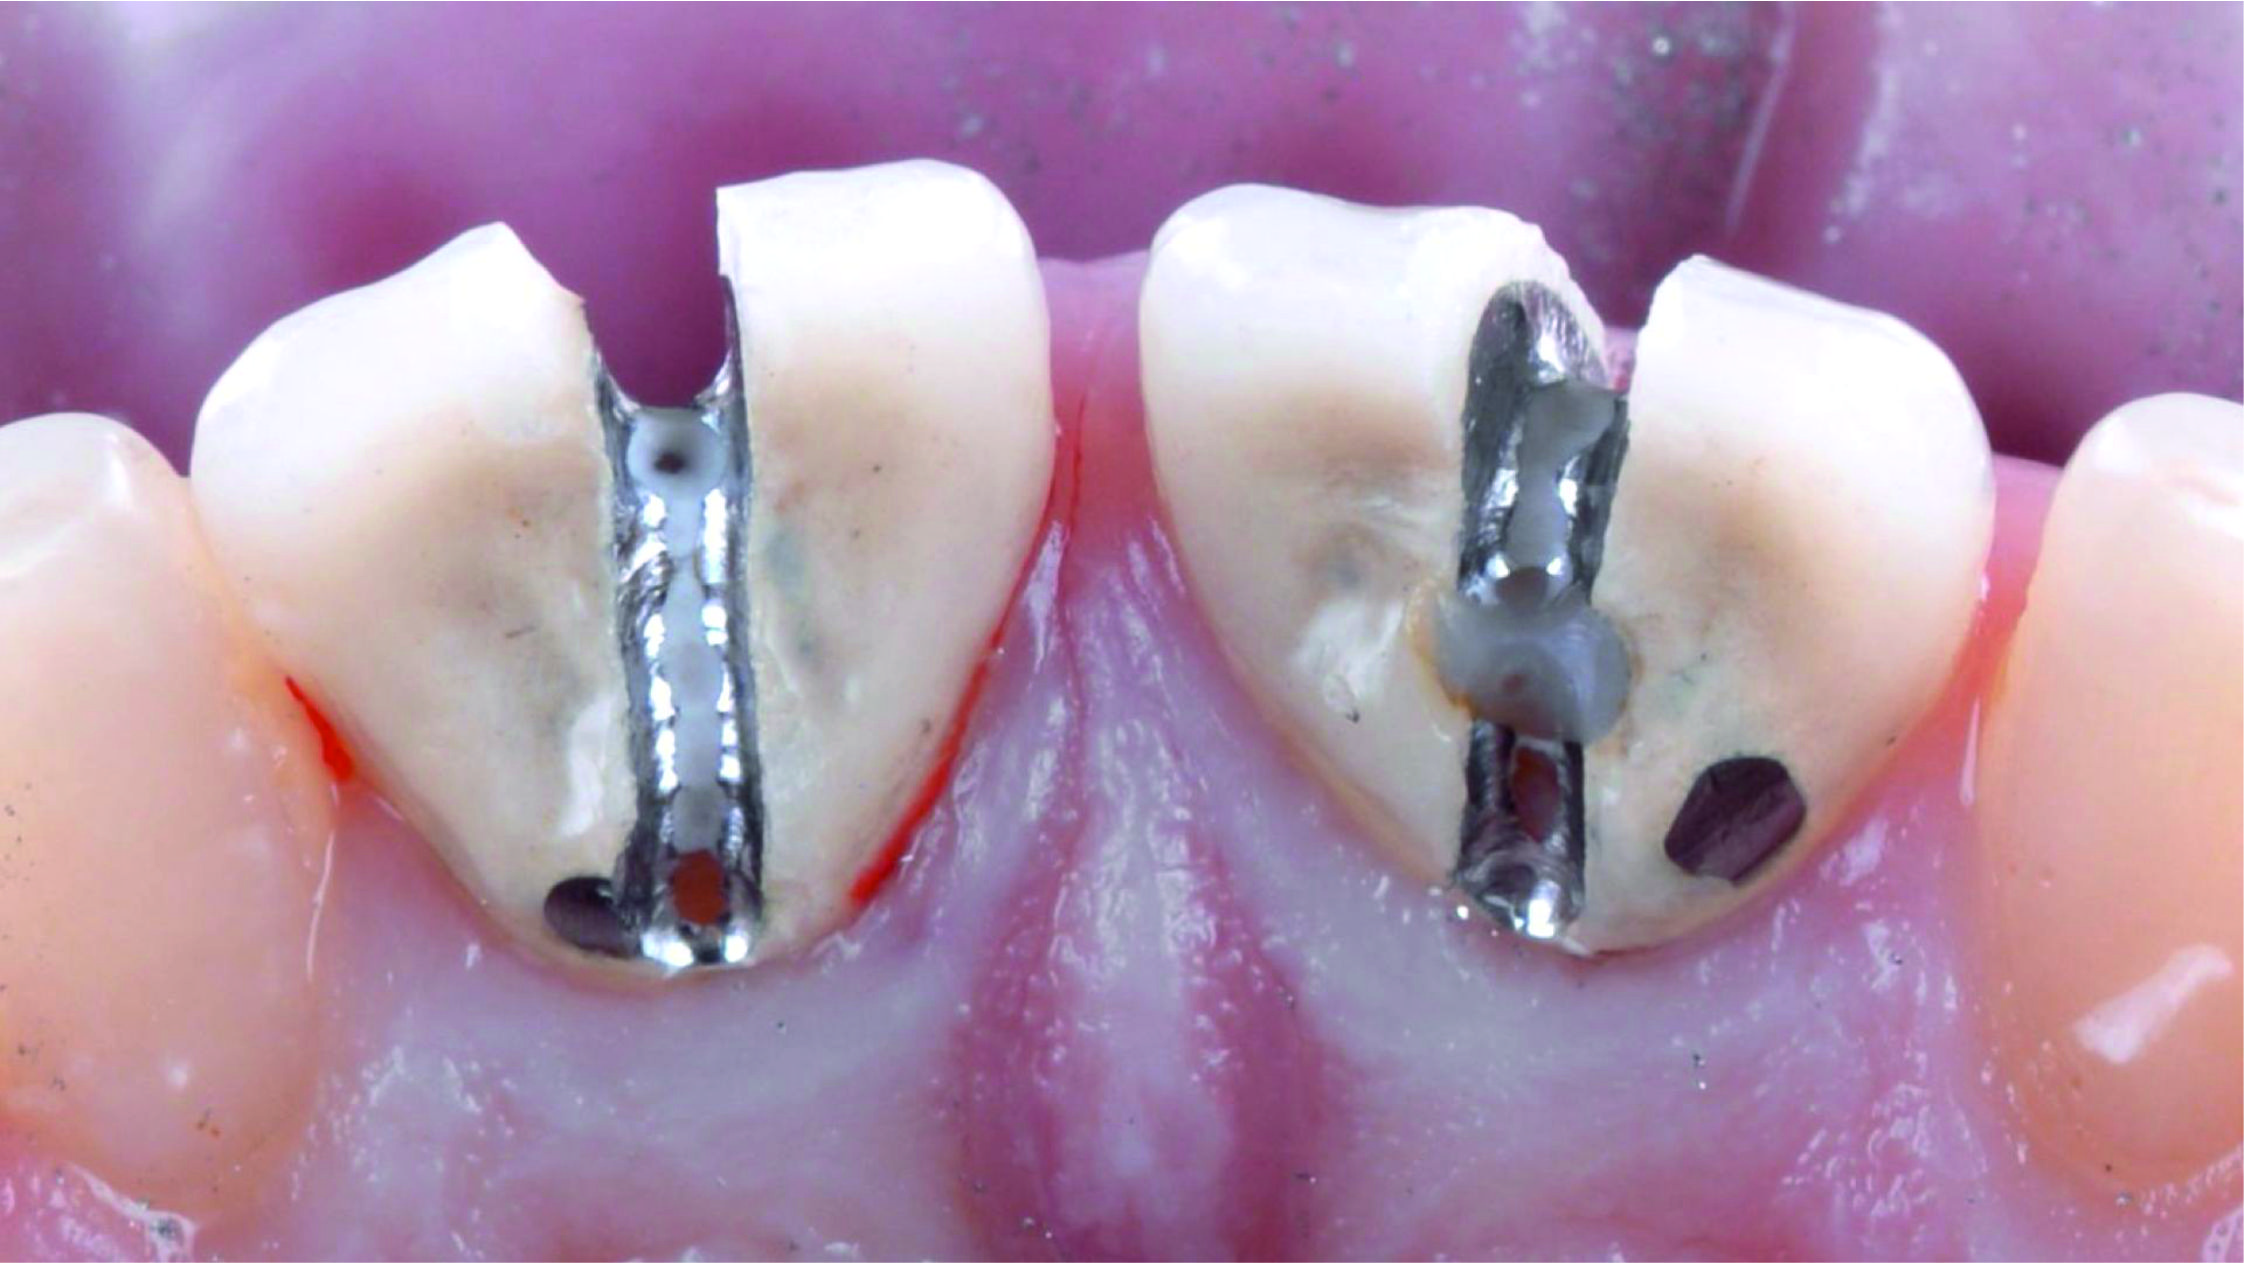

Фото 8. Після видалення штучних коронок видно, що кукси відпрепаровані з надлишком.Фото 9. Після усунення цементу, який залишився, та установки ретракційної нитки можна розглянути під’ясенну зону препарування, яка має різну глибину занурення, значно більше виражену в проксимальних ділянках кукс.

Фото 11. Кукси реконструювали за допомогою композитного матеріалу і заново відпрепарували на тому ж рівні висоти шийки, на якому вони були відпрепаровані раніше.